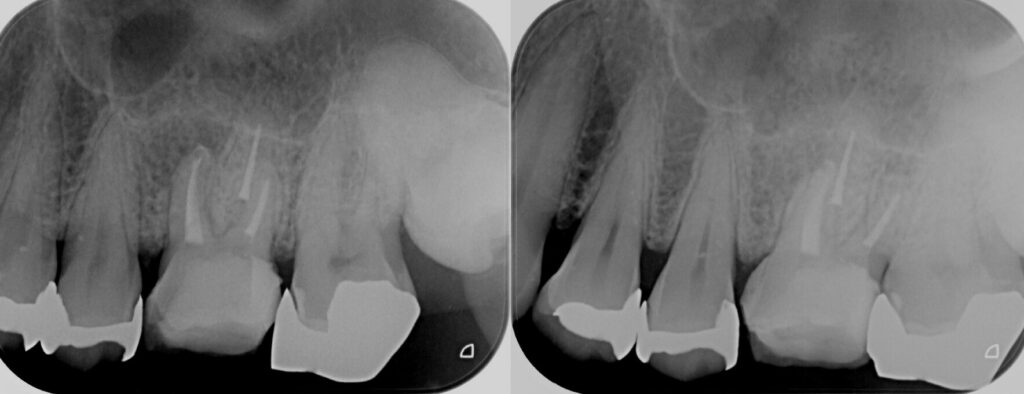

歯茎にできものができているとのことで来院、原因は昔他院で行った根管治療が奏功せずに根尖病巣が再発してしまっていたようです。

専門医での精密根管治療後、当院でセラミックの被せ物を行い虫歯の再発を防ぐ計画となりました。

現在は歯茎のできものもなくなり、白く美しい歯でご飯を食べていただけております。